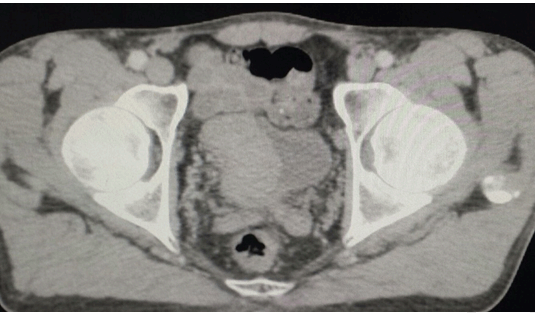

Cursor on image to zoom/Click text to open image

Figure 2: Contrast enhanced computed tomography scan of the pelvis in axial view demonstrating huge bladder mass.